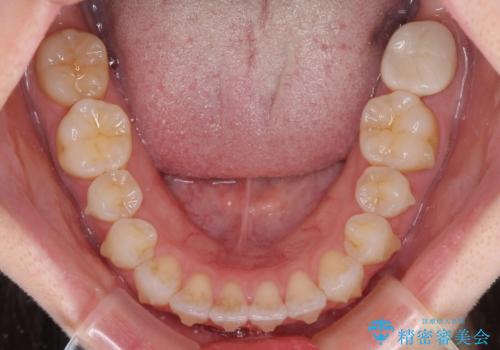

- 矯正治療の後戻りを気にして来院された患者様です。

後戻りは軽微でしたが、舌突出癖が認められ、初診時には上下前歯に舌がはまるスペースができていました。

舌突出癖の改善を行いながら、インビザライン・ライトにより矯正治療を行うこととしました。

舌突出癖の改善により上下前歯が接触するようになり、前歯でものを咬みきる必要のある食事がスムーズに行えるようになりました。